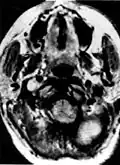

Glomus jugulare tumor -

Ectopic functional paraganglioma (glomus jugulare) in a patient with VHL. T2 weighted MRI at the same location demonstrates a high signal mass consistent with a paraganglioma. Extra adrenal paragangliomas can be found in VHL (arrow). -